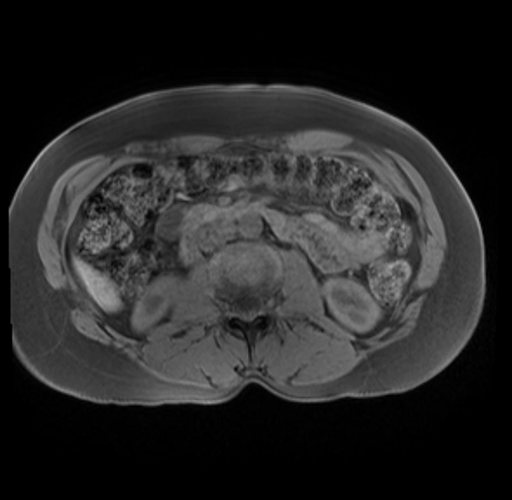

Imaging Analysis

Look through the patient's CT scan to identify any areas of concern for the necessary procedure.

Based on your CT findings, which issue(s) are present and would give reason for "planned slowing down moment(s)" in this case?